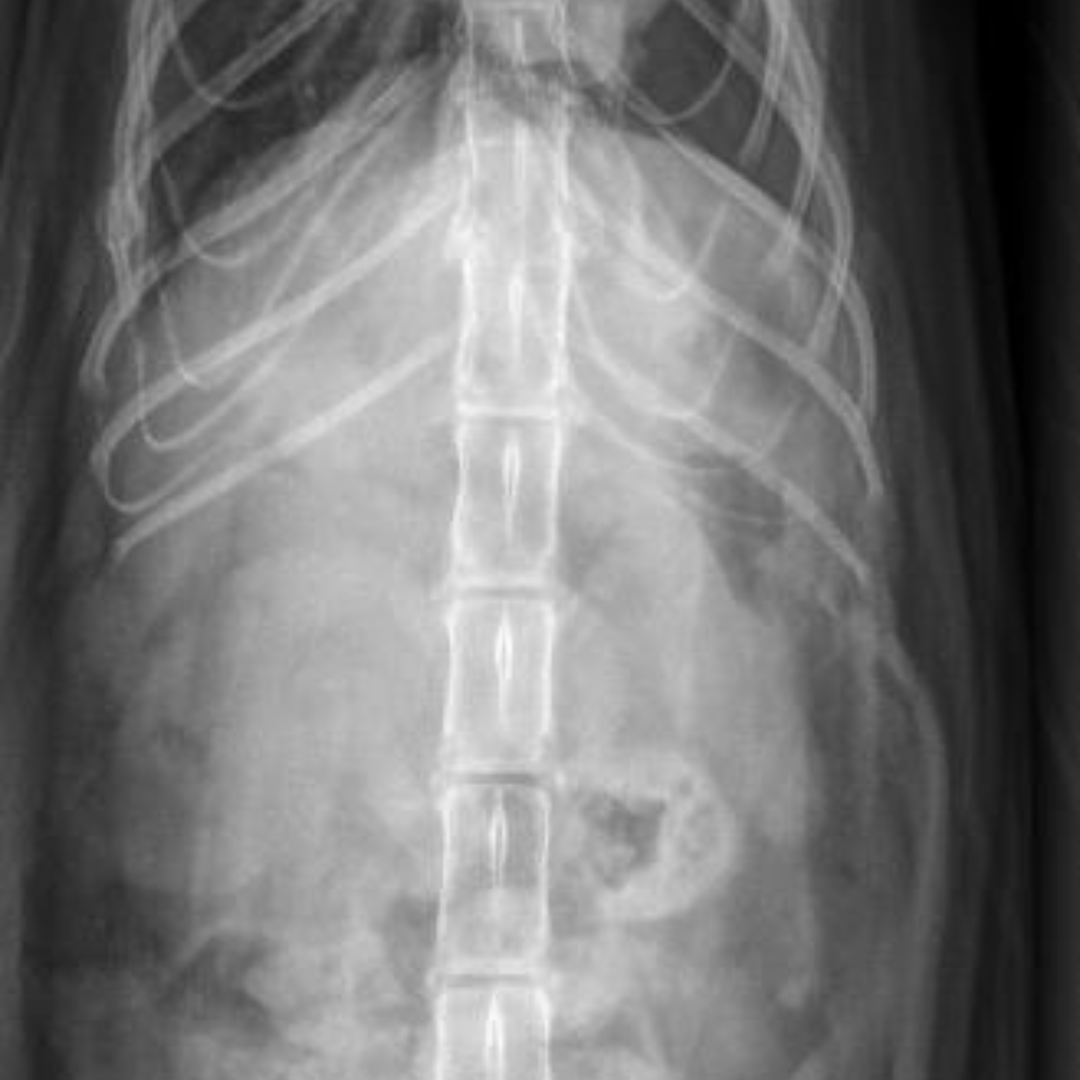

Our veterinary team at the Bredel Clinic acted quickly. Diagnostic X-rays revealed a diaphragmatic hernia, along with concern for a possible internal tumor or an enlarged kidney. A diaphragmatic hernia, as seen in the X-rays below, occurs when a rupture in the diaphragm allows abdominal organs, such as the liver, stomach, or intestines, to move into the chest cavity. This condition is most often caused by severe trauma, like being hit by a car or suffering a major fall, and it can lead to significant respiratory distress, rapid or shallow breathing, muffled heart and lung sounds, and chronic weight loss if left untreated.

During surgery, our veterinarians discovered that Raven’s kidney was severely enlarged, nearly double its normal size, and ultimately had to be removed. Additional scarring was found on her spleen, further confirming that she had likely suffered a significant traumatic injury in her past.